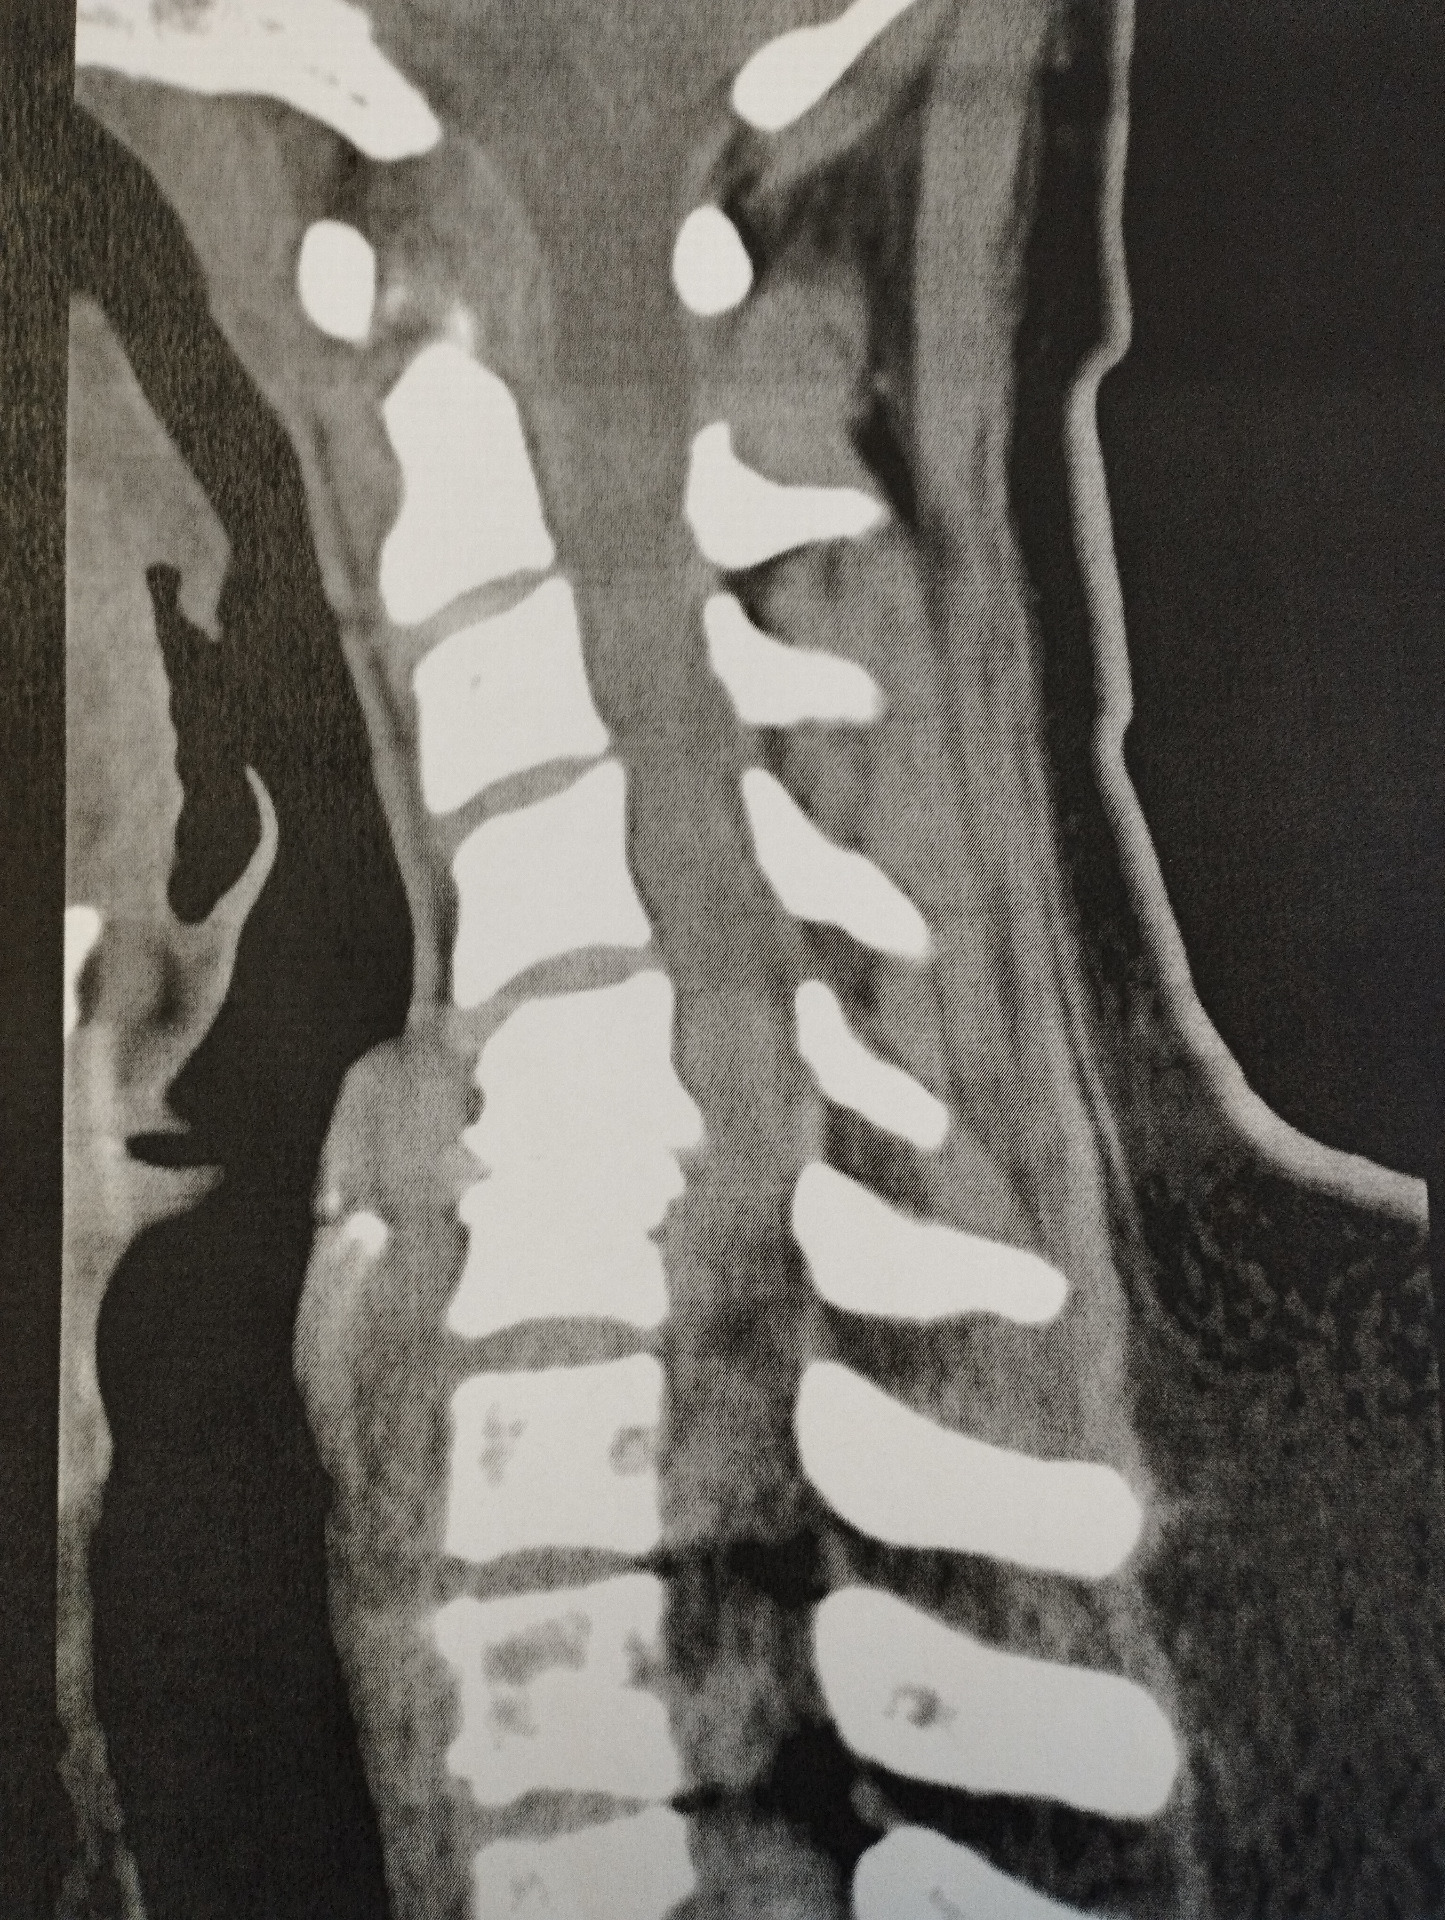

A doktornő miután megnézte az MRI felvételeit, csinált néhány manuális vizsgálatot a kezével és reflexkalapáccsal, majd közölte, hogy sürgősen meg kell műteni, mert a csigolyák nyomják a gerincvelőt, így egyetlen rosszul sikerült mozdulattól is lebénulhatnak a végtagjaim. Na, bumm!!! Január 9-ére elő is jegyezte az operációt. Van-e kérdésem?

Nem volt, mert akkor, ott leblokkoltunk mindketten a férjemmel. Igaz, hogy 8 évvel ezelőtt is mondták, hogy majd meg kell műteni, de egyáltalán nem tűnt égetőnek, hiszen 1 év táppénz után visszaküldtek dolgozni könnyített munkakörbe. (Ez az, amit nem talál egy idegen külföldön.) Még adott 3 beutalót az idegsebész olyan vizsgálatokra, amiket a műtét előtt kellett elvégezni a következő 2 hétben, az ünnepek alatt. December 27-én mentem kontrollra a röggel a fejemben, 29-én pedig még egy EMG vizsgálatra, konzultációra az altató orvossal és egy friss vérvételre. Január 3-án CT-re vitt a férjem, ahol azt nézték, hogy a nyaki csigolyáim mennyire vannak lemeszesedve.

A két hét állandó kattogással az agyamban telt, mivel nem kérdeztünk semmit a szakorvostól, ő nem is nagyon fejtegette, hogy mi fog velem történni. Nem érdeklődtünk, mert leblokkoltunk a sürgős operáció hírére, de időközben jöttek a kérdések, amikre az Interneten próbáltam válaszokat keresni.:( Mindössze annyit tudtam, hogy elöl fogják felnyitni a nyakamat, hogy hátra menjenek mikroszkopikus eszközökkel a nyakcsigolyákhoz. Azért elöl nyitják, hogy ne sértsék meg az idegeket, melyek a gerincoszlop mellett futnak, valamint a gerincvelőt. Kaptam egy műtéti leírást is a doktornőtől, azt próbáltam fordítgatni, és felfigyeltem egy bejegyzésre, miszerint +1 cage lesz beépítve a csigolyák közé.

Mi a túró az a cage? Szószerint: ketrec. Rákerestem. Igen, egy "ketrec" 2 csavarral, amit a széthúzott csigolyák közé tesznek és a csavarokkal rögzítik. Ekkor jött a következő kérdés. Mindenki állította, hogy atroszkópiás műtét lesz és a 2 kicsi lyuk a nyakamon nem is fog látszani. Hogyan lehetne 2 lyukon keresztül beépíteni egy ketrecet csavarokkal a nyakamba? Akármilyen fejlett az orvostudomány ezt nem tudtam elképzelni.